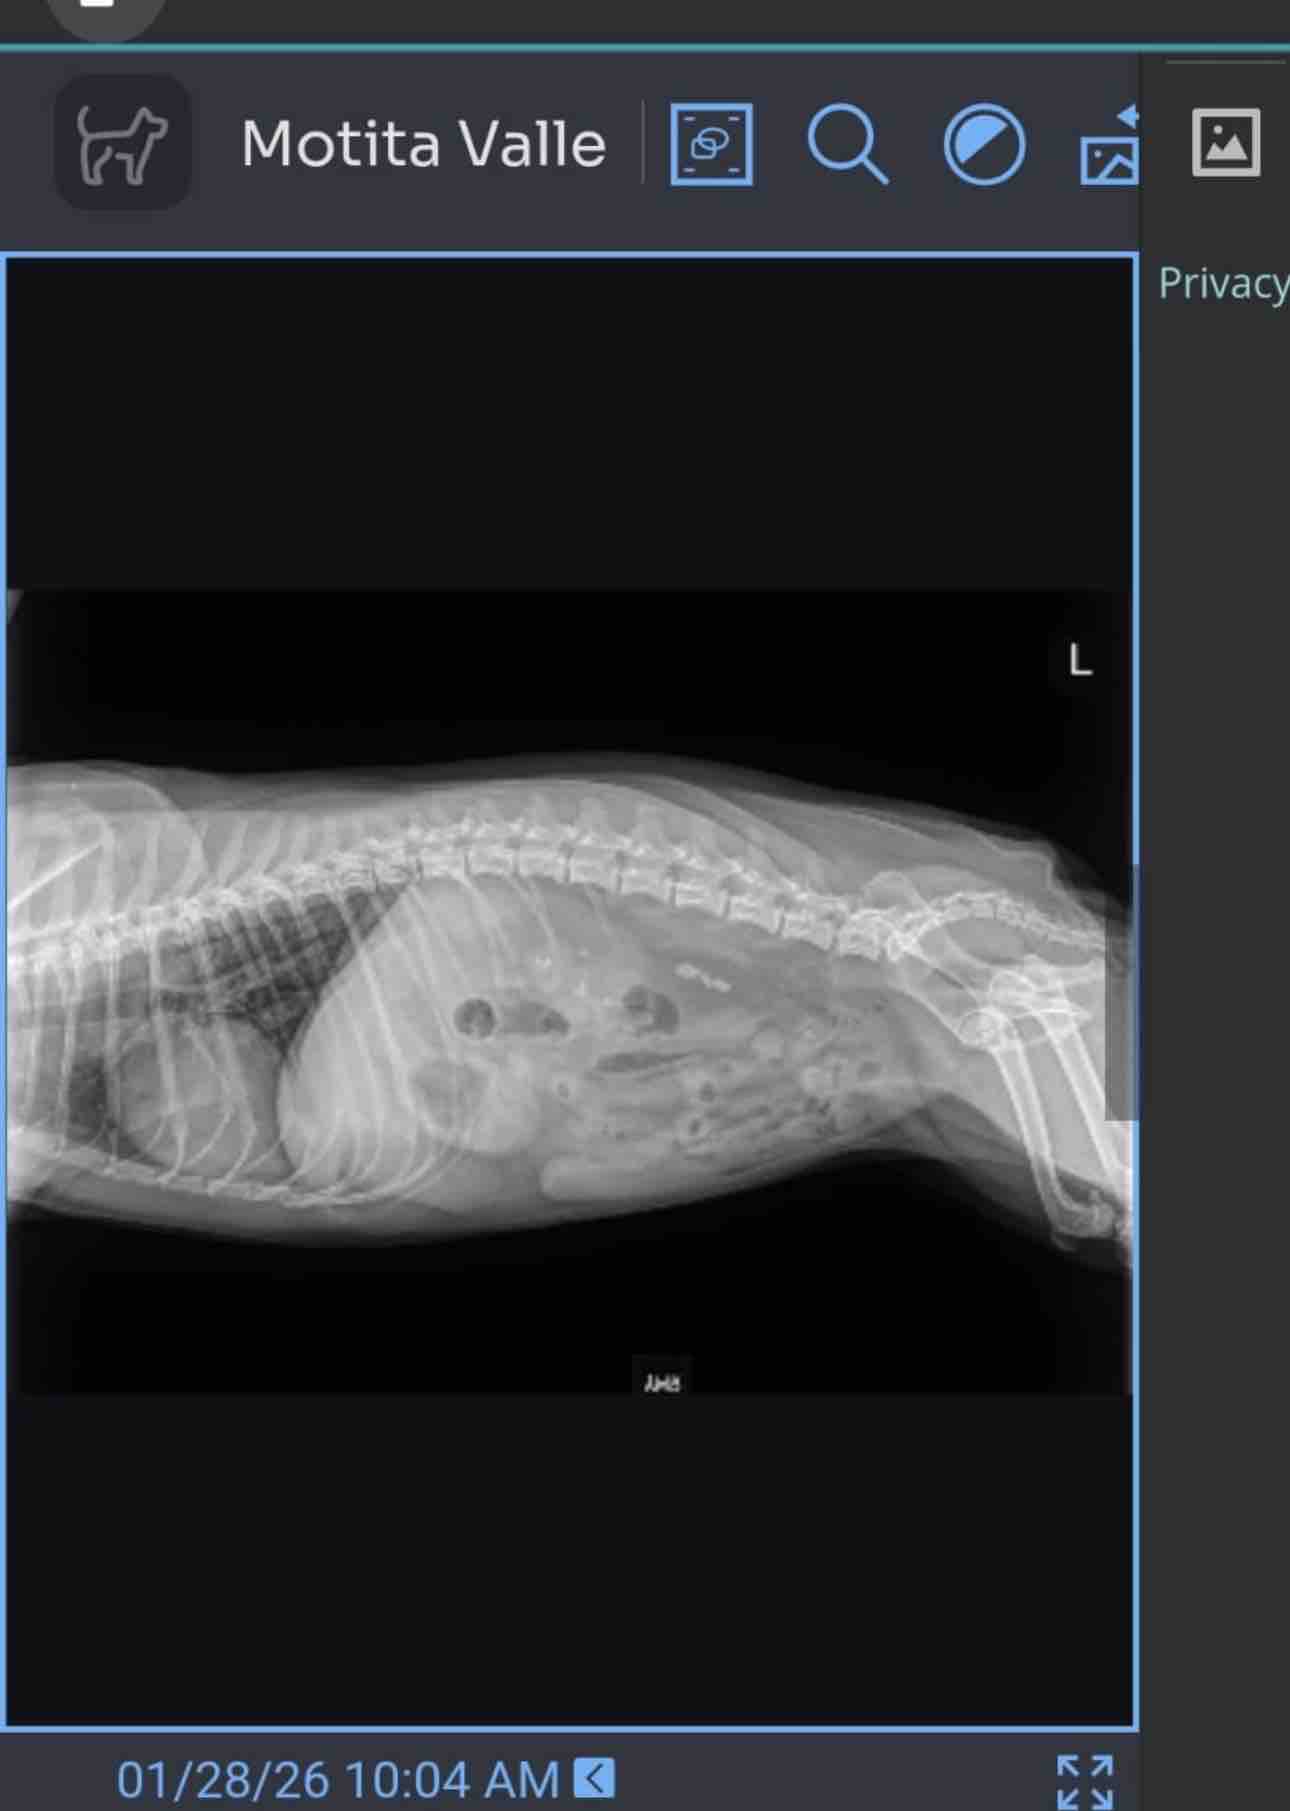

We are reaching out with heavy hearts for My Dear Friend Cinthya’s cherished Yorkie Terrier mix, who just turned nine years old. Last year, she underwent surgery for the same kidney stone issue, which cost $3,000 and required a loan that is still being repaid today. Now, unfortunately, she is facing the same problem once again, and the situation has become even more urgent.

Despite initial treatment with antibiotics and pain medications, her condition has worsened. She now suffers from pain, vomiting, and difficulty eliminating properly. The veterinarian has confirmed that she urgently needs surgery to remove the stones and prevent any life-threatening complications.